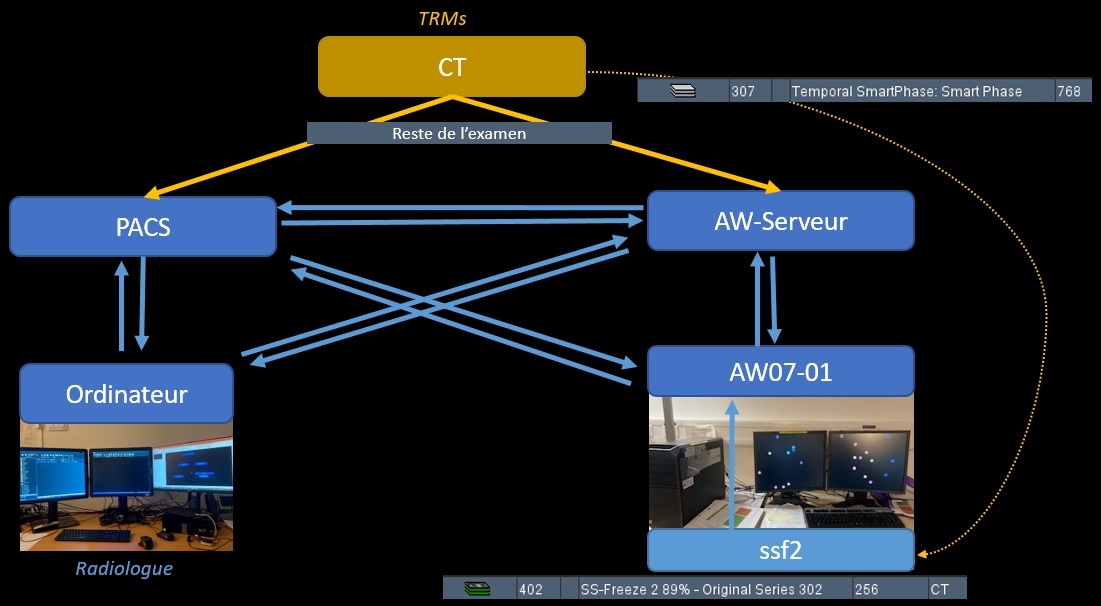

- Temporal SmartPhase = fais 3 séries, envoyer depuis le AW la SS-Freeze qui combine les trois, standard a 75%, mais la machine peut en trouver un ou ca bouge moins

Reconstruction AW Server

Reconstructions SS-Freeze